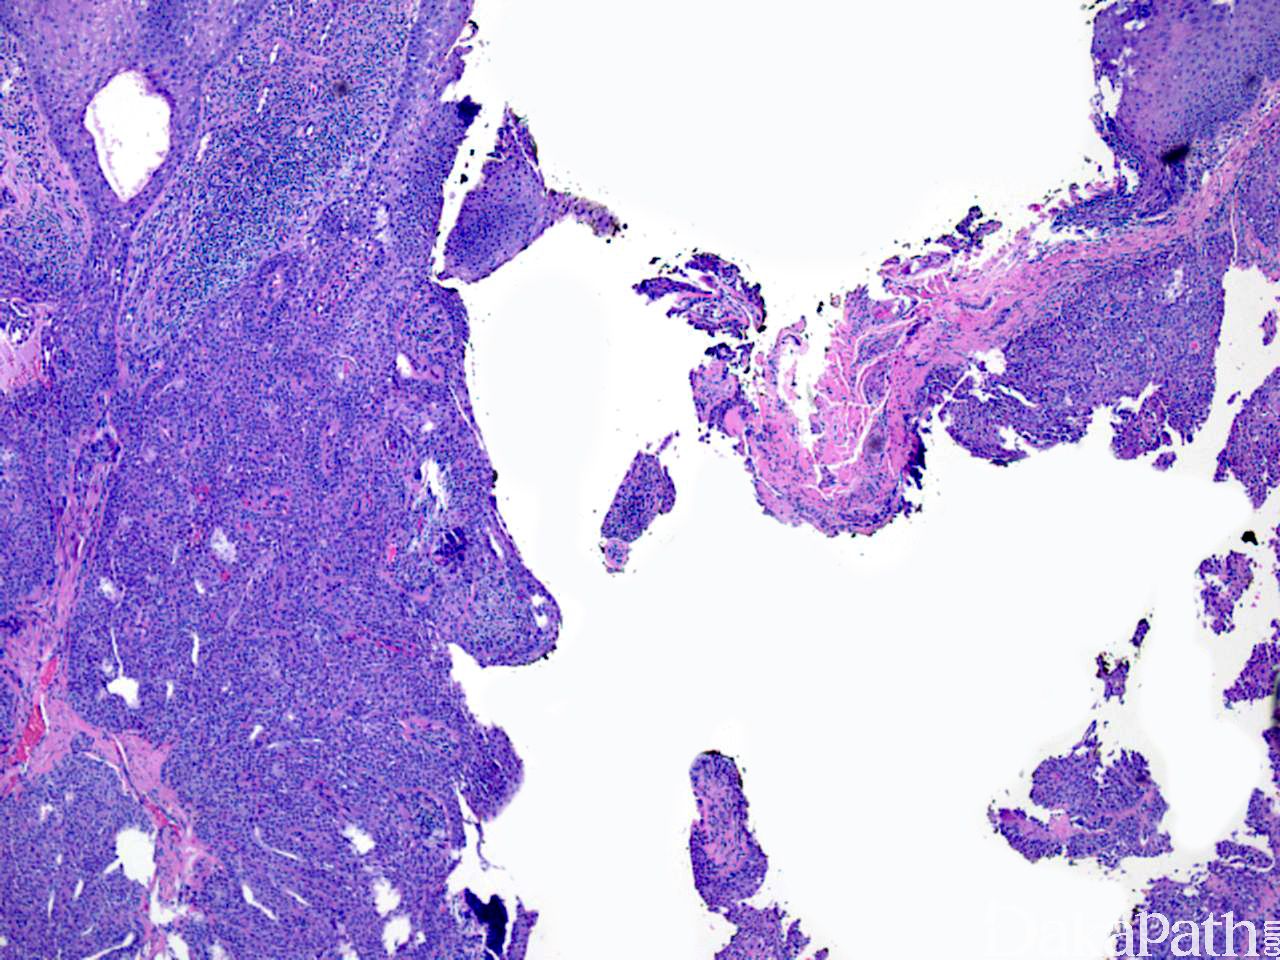

2. 大体检查见真皮内边界清晰多叶性肿瘤,有实性和囊性结构,直径可达 2cm 或更大;

3. 镜下:肿瘤界限清楚,位于真皮浅层,可与表皮相连,较大肿瘤可深达皮下组织;

5. 瘤体中有汗腺小管结构,可扩张呈囊性区域,囊内充满粉染无结构物,管腔或囊内衬立方导管细胞或柱状分泌细胞,核分裂少见。

6. 间质纤维化,并可出现广泛的玻璃样变性。